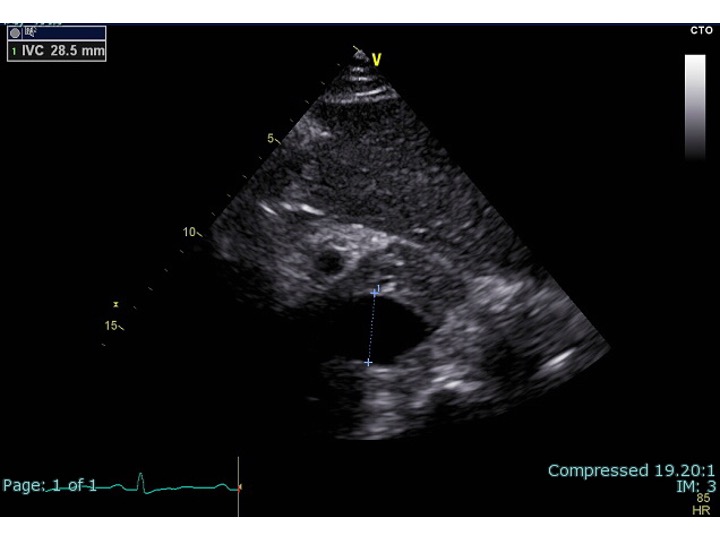

ransthoracic echocardiography was performed: Although the left ventricular ejection fraction was preserved, the inferior vena cava was dilated and showed no respiratory variation. There were pericardial adhesion and a septal bounce (Fig2-4). He was suspected of having constrictive pericarditis and was admitted for further evaluation.